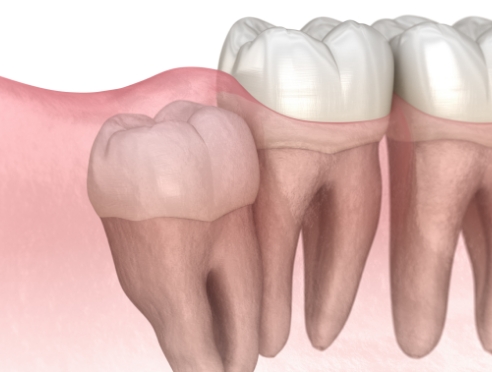

3D CT로 사랑니의 방향, 신경 위치, 주변 치아와의 관계를 세밀하게 확인한 뒤 필요한 경우에 한해 발치를 진행합니다.

불필요한 조직 손상을 최소화하는 방식으로 부담을 줄이며, 환자분이 보다 편안하게 회복하실 수 있도록 돕고 있습니다.